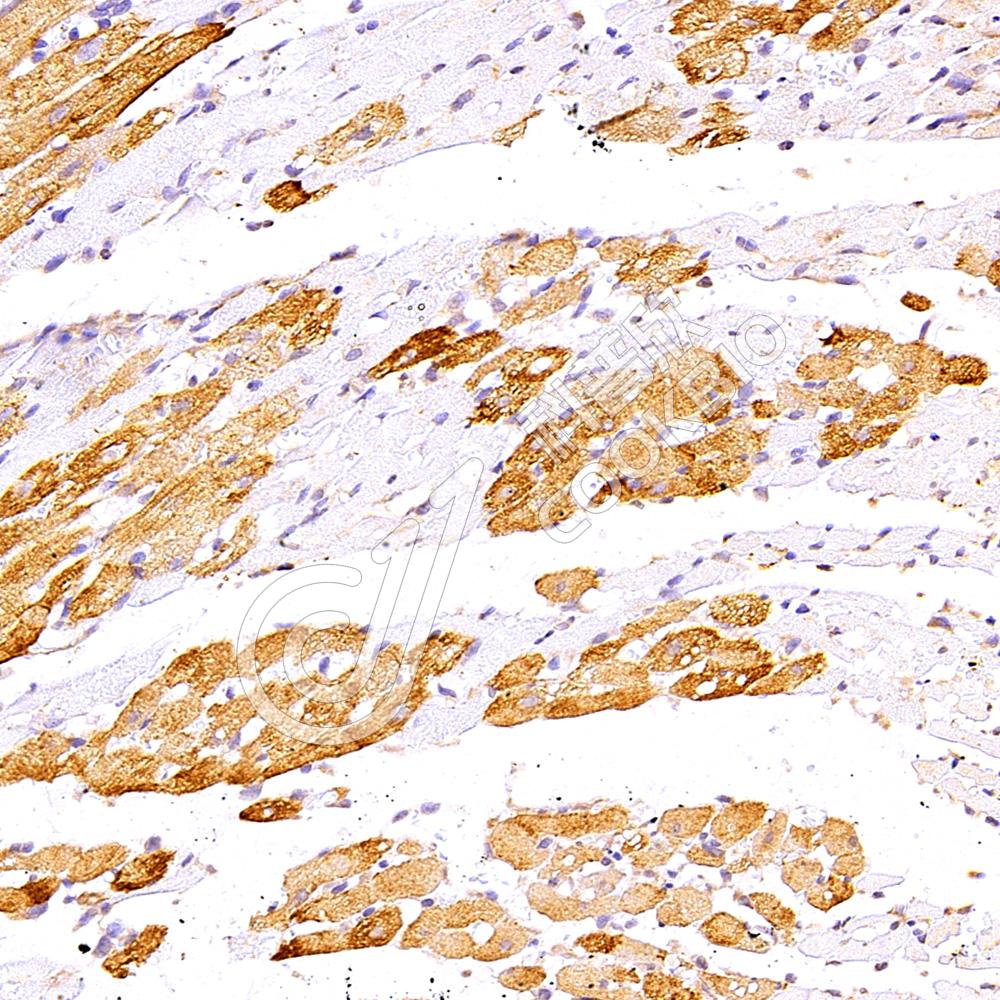

IHC检测Cardiac Troponin I蛋白(货号 K1337224).

样品: 小鼠心脏缺血再灌注损伤, 4%多聚甲醛 (货号KSG1101) 固定12-24小时.

抗原修复: 柠檬酸抗原修复液(干粉, pH 6.0) (KSG1201), 98℃, 20分钟.

—抗: 1: 300稀释, 4℃ 孵育过夜.

二抗: S-vision免疫组化多聚二抗(山羊抗兔),即用型 (货号KB3906), 室温孵育20分钟.

样品: 大鼠心脏缺血再灌注损伤, 4%多聚甲醛 (货号KSG1101) 固定12-24小时.